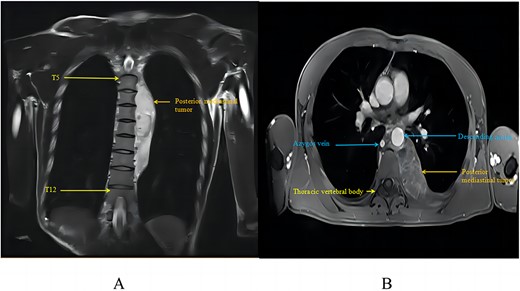

At that time, evaluation with chest CT and magnetic resonance imaging (MRI) identified a large, strip-like soft tissue mass in the left posterior mediastinum. It was adjacent to the thoracic intervertebral foramen, encircled the descending aorta’s posterior wall, and extended into the right mediastinum, affecting the azygos vein. Positron emission tomography-computed tomography (PET-CT) showed a 65 × 32 mm sized mass with increased uptake (SUV max 2.2). MRI showed a mass with mixed signals on T1WI, high signals on T2WI, and localized cystic areas, suggesting a neurogenic tumour (Fig. 1).

Posterior mediastinal haemangioma as seen on chest MRI: (A) tumour in MRI coronal view; (B) tumour in MRI axial view.